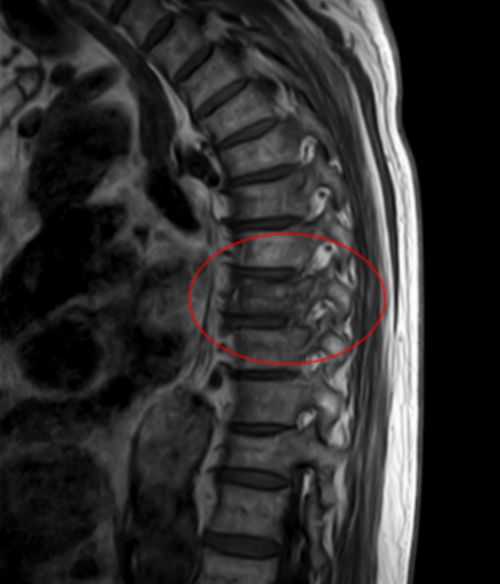

核磁共振显示王大爷T8胸椎压缩性骨折

据家属回忆,早在几年前,社区医生就提醒过老人,体检结果显示他有骨质疏松,需要重视。但老人自认为身体很健康,没太重视,直到这次因为举杠铃导致T8胸椎压缩性骨折入院,老人才认识到骨质疏松的危害。

脊柱外科二区主任曾浩介绍,王武成老人骨折的原因,并非简单的动作失误造成的,其根本在于老年性骨质疏松。骨骼如同建筑的钢筋,随着年龄增长,尤其是老年人,骨量自然流失,骨骼退化,导致骨密度下降、骨骼脆性增加。此时,骨骼承受外力的能力显著降低。像打沙袋瞬间的冲击力、举杠铃时脊柱承受的垂直压力,对于已骨质疏松的脊柱来说,可能已超出了安全负荷,从而引发骨折。尽管老人一直坚持健身,看上去身体很“硬朗”,但其骨骼的内部结构,已悄然进入了需要特别呵护的“脆弱期”。此外,还有一个不容忽视的原因:王大爷体重高达160斤,大基数使得骨骼同样长期受压,加剧了脊柱负担,更易致骨折。